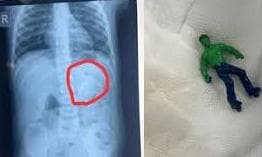

Toddler Swallows Hulk Toy; Doctors Remove Toy Via Endoscopy

Ahmedabad : Doctors at a government hospital in Ahmedabad have removed an entire plastic toy that a toddler had swallowed, which could have potentially damaged his intestines, an official said on Wednesday. The one-and-a-half-year-old boy had a small 'Hulk' toy, based on a popular comic superhero, stuck in his stomach when his parents brought him to the Civil Hospital, said Dr Rakesh Joshi, Head of the Department of Pediatric Surgery. The toy was removed entirely through upper GI endoscopy, Dr Joshi said. "Had it been a little late, the toy could have moved further from the stomach and got stuck in the intestines. In that case, there would have been a risk of intestinal blockage and even rupture," the senior doctor said. On January 18, Dr Joshi said, the child's mother found her son vomiting and in distress. She became anxious after realising that one of his toys was missing. Fearing that the toddler had swallowed his "green Hulk", the family rushed him to the Civil Hospital, where doctors were stunned when an X-ray showed the entire toy in the stomach. Dr Joshi said the toy stuck in the child's stomach was not a piece but a full-sized character with arms, legs and a head. "There is a natural valve between the oesophagus and the stomach. The biggest challenge was to take out a whole toy through this valve. When we tried to grab it with the endoscope, the toy kept slipping because of the air in the stomach. "Pulling the toy by its hand or foot raised the possibility of it getting stuck in the valve and causing it permanent damage," he said. After a lot of effort, the doctors managed to hold the head of the toy and pulled it out, Dr Joshi said. Had the toy slipped down, there was a risk of the intestine rupturing, necessitating an operation, he said. The procedure was conducted on January 19, and the child is now completely healthy, the official added.